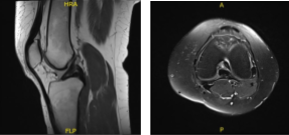

MRI results were presented and shown single slice visualization of a small medial meniscus tear. Trace joint effusion. The ACL is unremarkable, without evidence of tear, degeneration, or postoperative change.

MRI -3 T Left Knee Non-contrast